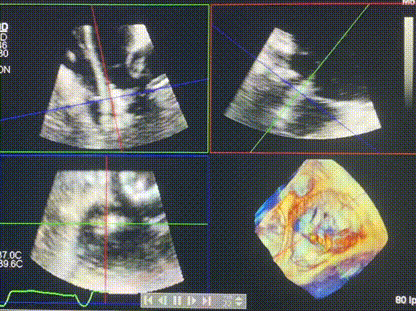

術(shù)中輸送器在超聲引導下調(diào)整位置

手術(shù)在全麻狀態(tài)下進行。術(shù)者采用經(jīng)右側(cè)頸靜脈入路的方式將輸送器送入患者心臟內(nèi),在TEE及DSA引導下調(diào)整輸送器頭端角度,使得輸送器與三尖瓣瓣環(huán)平面垂直。在輸送器進入右心室后釋放室間隔錨定裝置,而后釋放瓣葉夾持件(2個耳片結(jié)構(gòu))成垂直狀態(tài)。在TEE及DSA確定夾持件固定至三尖瓣葉根部且位于右室側(cè)后釋放人工瓣心房側(cè)盤片。隨后調(diào)整瓣膜同軸性以及室間隔錨定件位置(貼合室間隔),前推藏針管并固定,進而釋放室間隔錨定裝置,并再次確認瓣膜位置、穩(wěn)定性及同軸性,合攏輸送鞘后撤出輸送器,完成LuX-Valve Plus人工三尖瓣瓣膜的植入,僅殘余微量瓣周漏。且經(jīng)手術(shù)中心電生理團隊評估,病人的起搏器和ICD功能沒有受到影響。

術(shù)后超聲顯示僅殘余微量瓣周漏